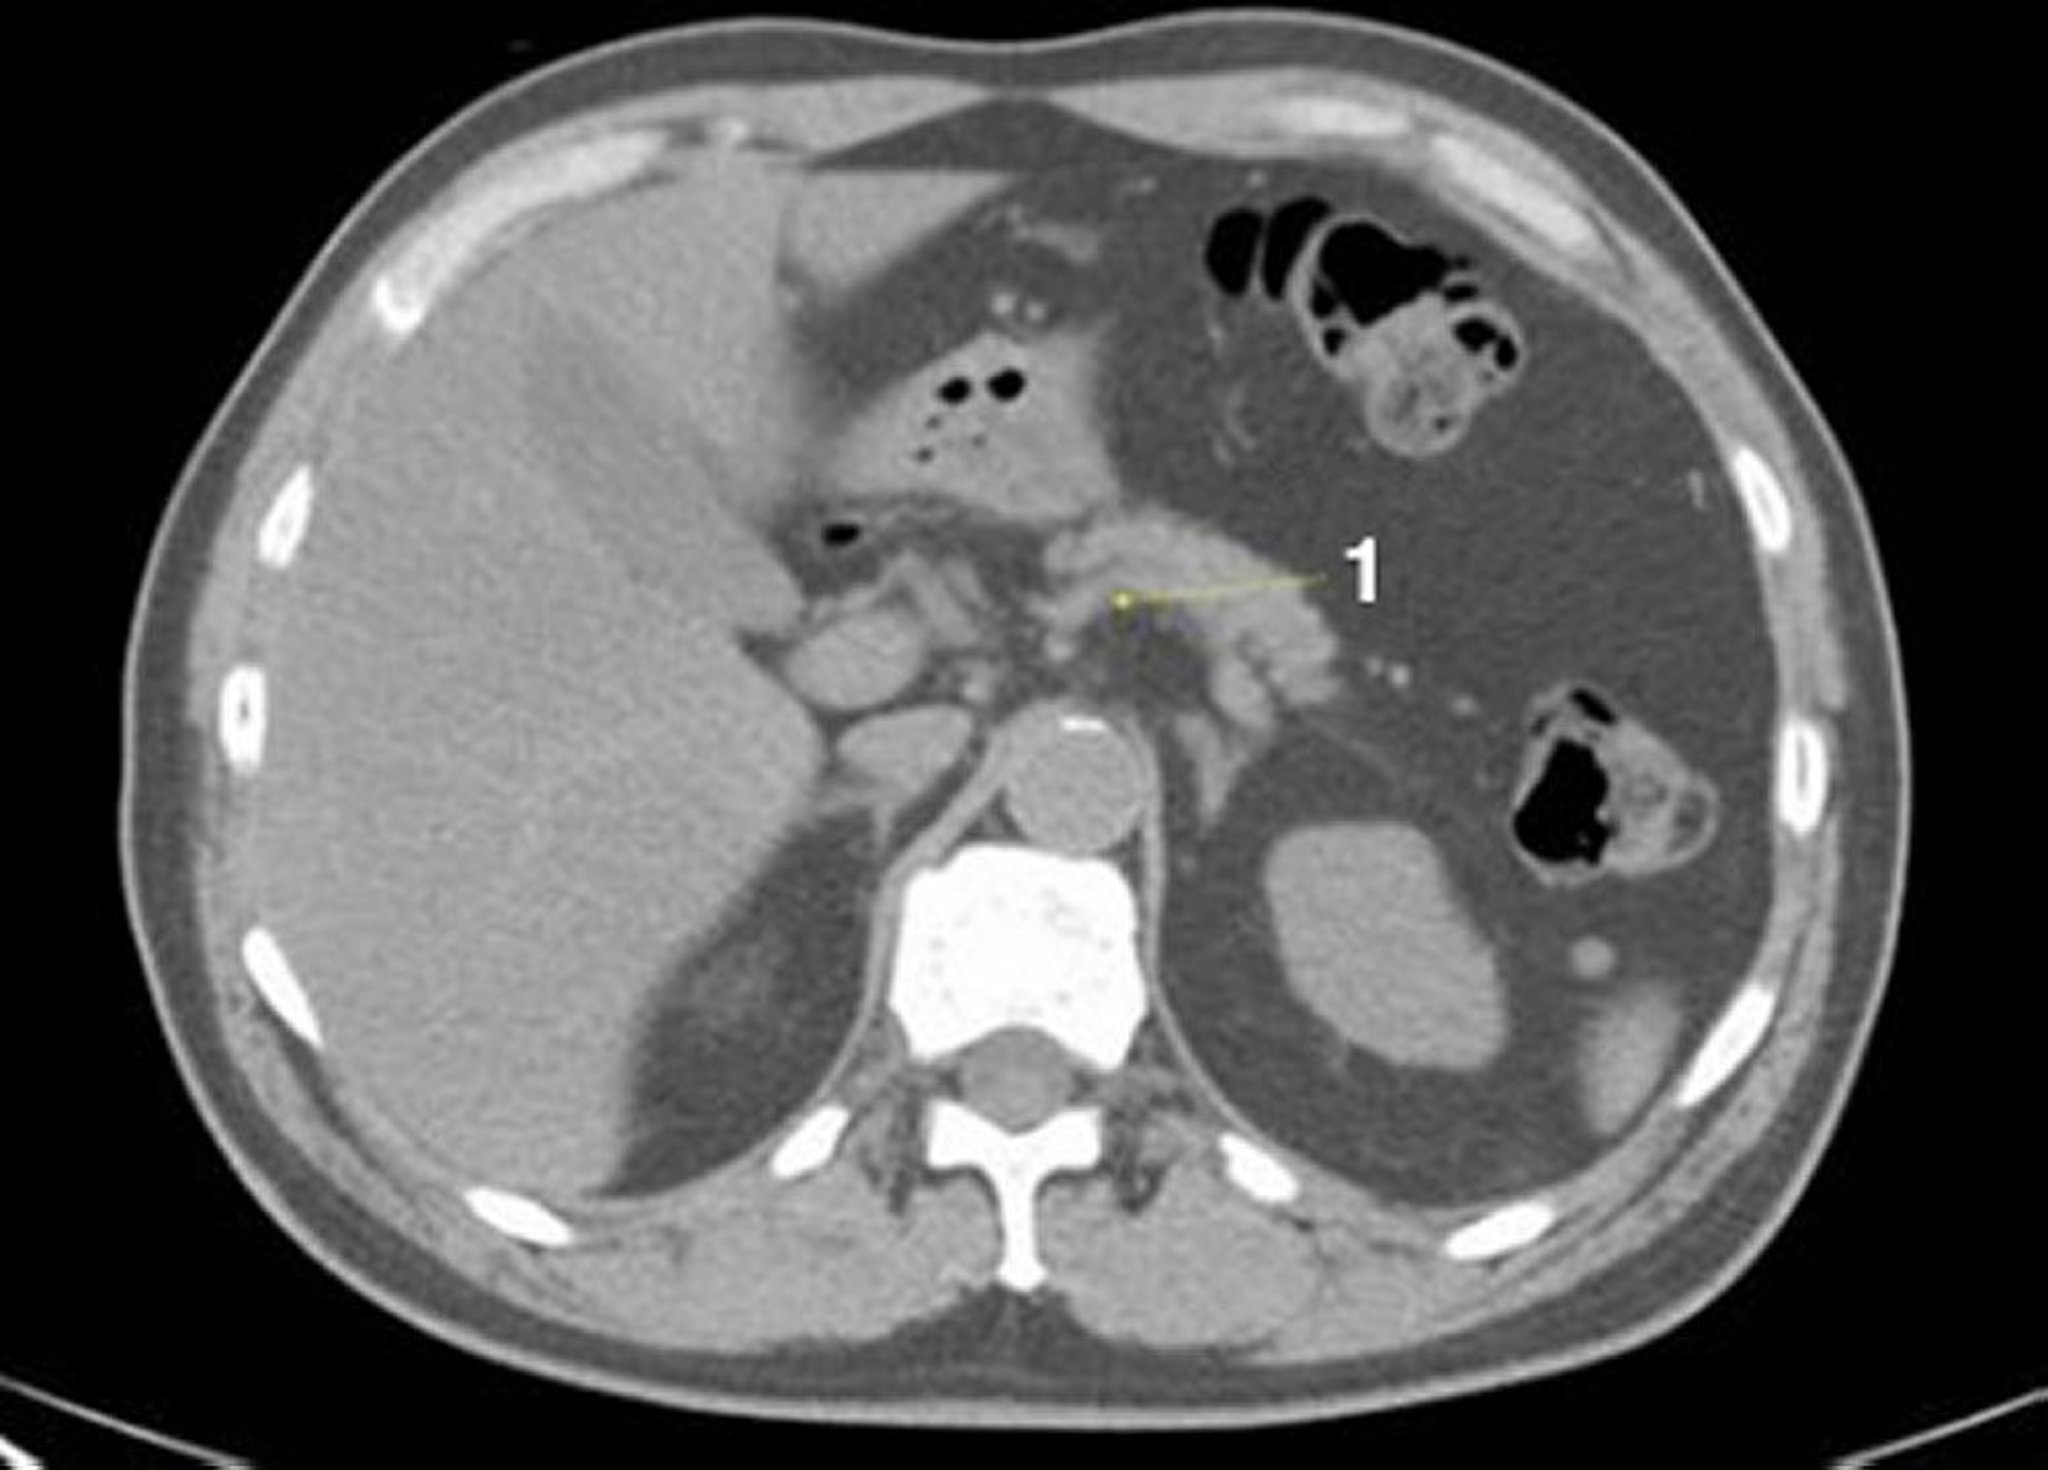

TC senza contrasto dell'addome e della pelvi che mostra un'anatomia normale (Slide 7)

1 = vena splenica.